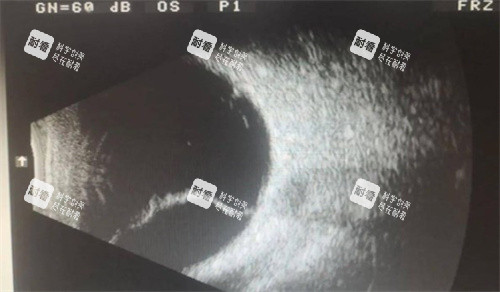

有位患者,因为高度近视导致视网膜脱离,视力急剧下降,几乎看不见东西。他辗转多家医院,都被告知手术难度大、风险高。后来,他找到了黎晓新医生。黎医生仔细检查后,为他制定了个性化的手术方案:可靠行27G小创口玻璃体切割术,切除混浊的玻璃体,再精密复位视网膜,然后用激光光凝封闭裂孔。手术非常顺利,术后患者的视力逐渐修复,现在已经能正常生活和工作了。他说:“黎医生不仅技术好,还特别耐心,让我从绝望中看到了希望。”